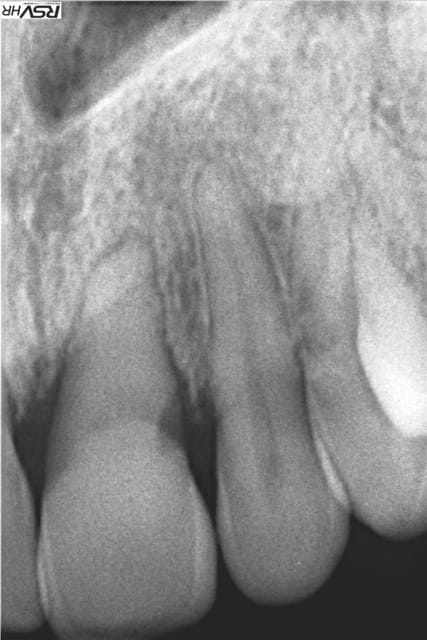

Bonjour à tous, patiente de 25 ans se présentant avec une mobilité de la 21.Je prends la Rx et constate cette resorption+disparition pulpe(trt ortho? ,n'a pas de souvenir d'un choc).J'ai proposé une contention et une surveillance (avec plus tard pose d'implant)/

sur la première radio, il me semble aussi que la 11 est touchée (en distal) et de toutes façons la racine est elle aussi bien rhizalysée...

Bonjour, il semblerait qu'il existe un sérieux problème parodontal au vu des pertes d'attaches des 11 et 21, à 25 ans.

Penses-tu que ce n'est pas à considérer avant de se focaliser sur 21 et traitement implantaire ?